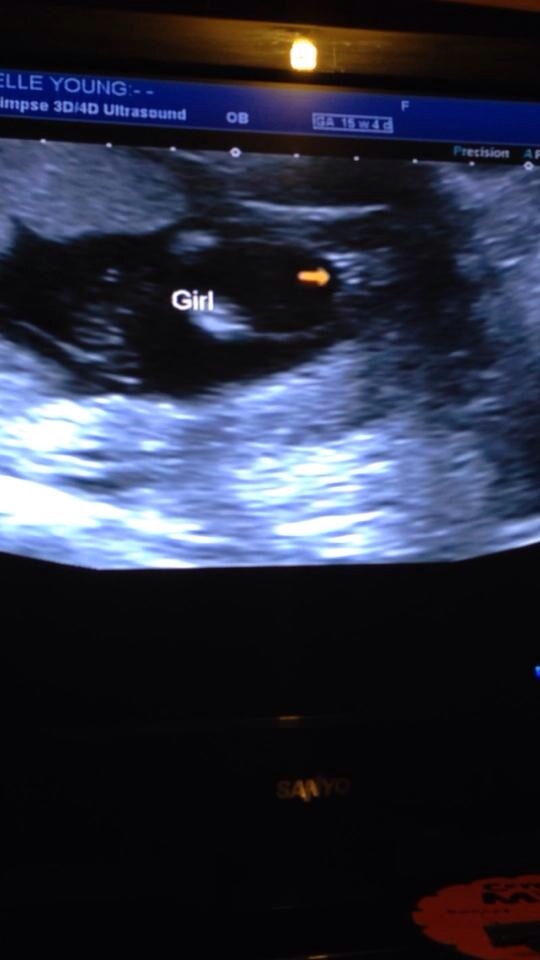

IT'S A GIRL!! 15w4days and SO clear!

15w4days

Hard to see in the photos but in the video it is so obvious! My little miss was not shy and had her legs wide open. The tech looked at it from all angles just to be sure but we could all see it was definitely a little giney - no penis in sight, just three clear lines! We even checked in 3d. It was the best scan ever and so thorough.